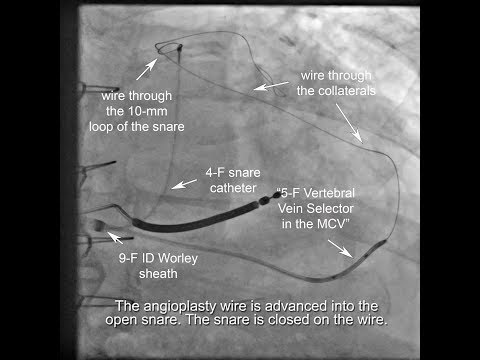

Antidromic snare + Venoplasty + use of micro catheter inside vein selector to traverse collaterals